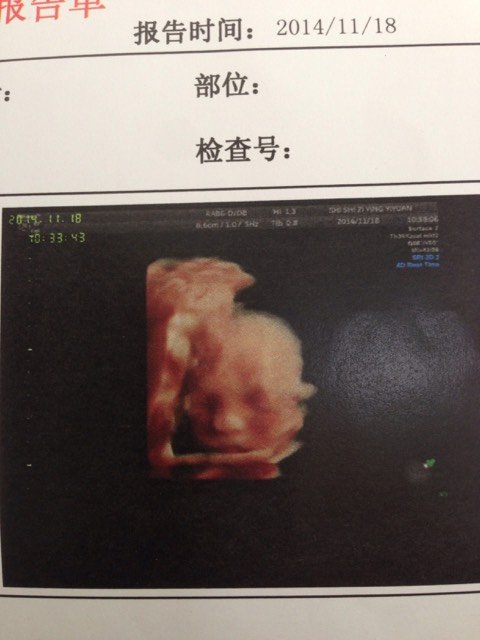

双顶颈64mm,头围233mm,股骨长46mm,腹围199mm,肱骨43mm,羊水最大深度59mm 双顶颈64mm,头围233mm,股骨长46mm,腹围199mm,肱骨43mm,羊水最大深度59mm,胎儿体重762g 土111g!这样宝宝大概有多大啊?羊水这些正常吗?🙏 点击展开 苏粉粉的微博 2014-11-18 18:31 为您推荐: 其他回答 ,,,,, hanhan 2014-11-18 22:54 很好啊,, 晋铭妈妈 2014-11-18 20:41 数据什么的一切都正常 乐乐不是我 2014-11-18 19:36 对啊,你有多少周啦 掌心的太阳 2014-11-18 19:00 我的有800多克了 掌心的太阳 2014-11-18 18:59 加载更多 相关问题 双顶颈81mm,头围296mm,腹围287mm,股骨长62mm,胎盘厚度33mm,羊水最大深度6 超预产期一周胎盘成熟度两级羊水最大暗区深度36mm 双顶颈92脐带绕颈两周能顺产吗 怀孕已经38周,脐带绕颈两周,羊水深度3 3,双顶颈8 8,其他正常,但胎心检测很好,想问下能否顺产?